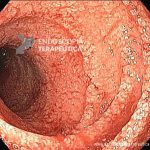

Estrongiloidíase duodenal

- Duodeno com edema, enantema, friabilidade e sangramento espontâneo.

- Duodeno com edema de criptas, friabilidade e sangramento espontâneo, observados ao NBI (narrow band imaging).